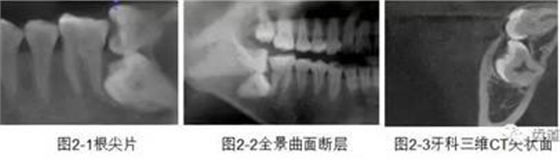

CBCT在牙體牙髓病科治療中,對牙根周圍的解剖關(guān)系、炎癥病變、囊腫等就能夠輕而易舉的進(jìn)行診斷。甚至與牙齒內(nèi)根管的數(shù)目、走向、分支等都能夠通過牙科CT進(jìn)行展示,使臨床醫(yī)生的根管治療不再是完全憑手感的“經(jīng)驗(yàn)科學(xué)”。通過CBCT,還可以對一些“久治不愈“的疑難病例進(jìn)行檢查和診斷,例如根縱列的診斷、根管內(nèi)異物的定位等,找準(zhǔn)了原因,結(jié)合先進(jìn)的治療技術(shù)因病施治,使疑難病例的治療變的輕松起來。

1、牙髓根管治療

1)根管治療中牙膠尖充填在CBCT中的影像

2)根管測量